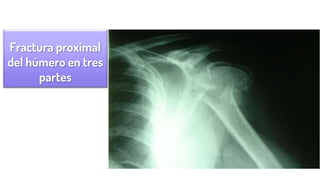

Fractura proximal

del húmero en tres

partes